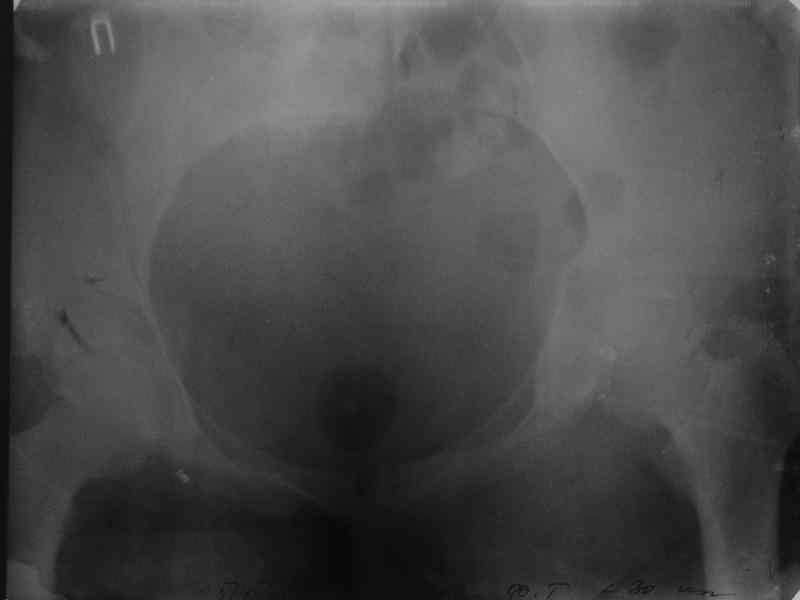

Молодая девушка 19 лет, травма 1 год назад, тогда же прооперирована.

В приложении снимки при поступлении и послеоперационные год назад.

Могу сказать одно: миграция винтов и нестабильность синтеза левого подвздошно-крестцовогоо сочленения очевидна.

Забыл добавить, что ИХМО показан реостеосинтез более длинными винтами, с более широкой резьбой, с фиксацией за правое подвдошно-крестцовое сочленение.